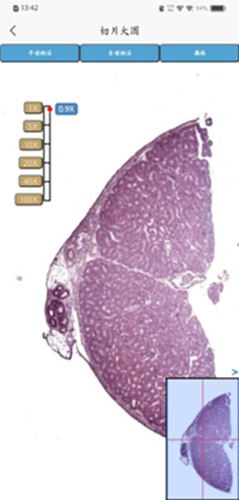

Turingene电脑版介绍:Turingene是一款专为病理诊断设计的移动应用程序。由苏州迪美格智能科技有限公司开发,它允许用户通过手机扫描病理切片,并将扫描结果方便地分享给其他用户。这项功能可以帮助病理医生更高效地进行病情诊断,提高医疗效率。

Turingene是一款由苏州迪美格智能科技有限公司自主研发的App,用户可以通过此App,进行病理切片的扫描,扫描完成的切片可以进行内外部分享,协助病理医生病情诊断